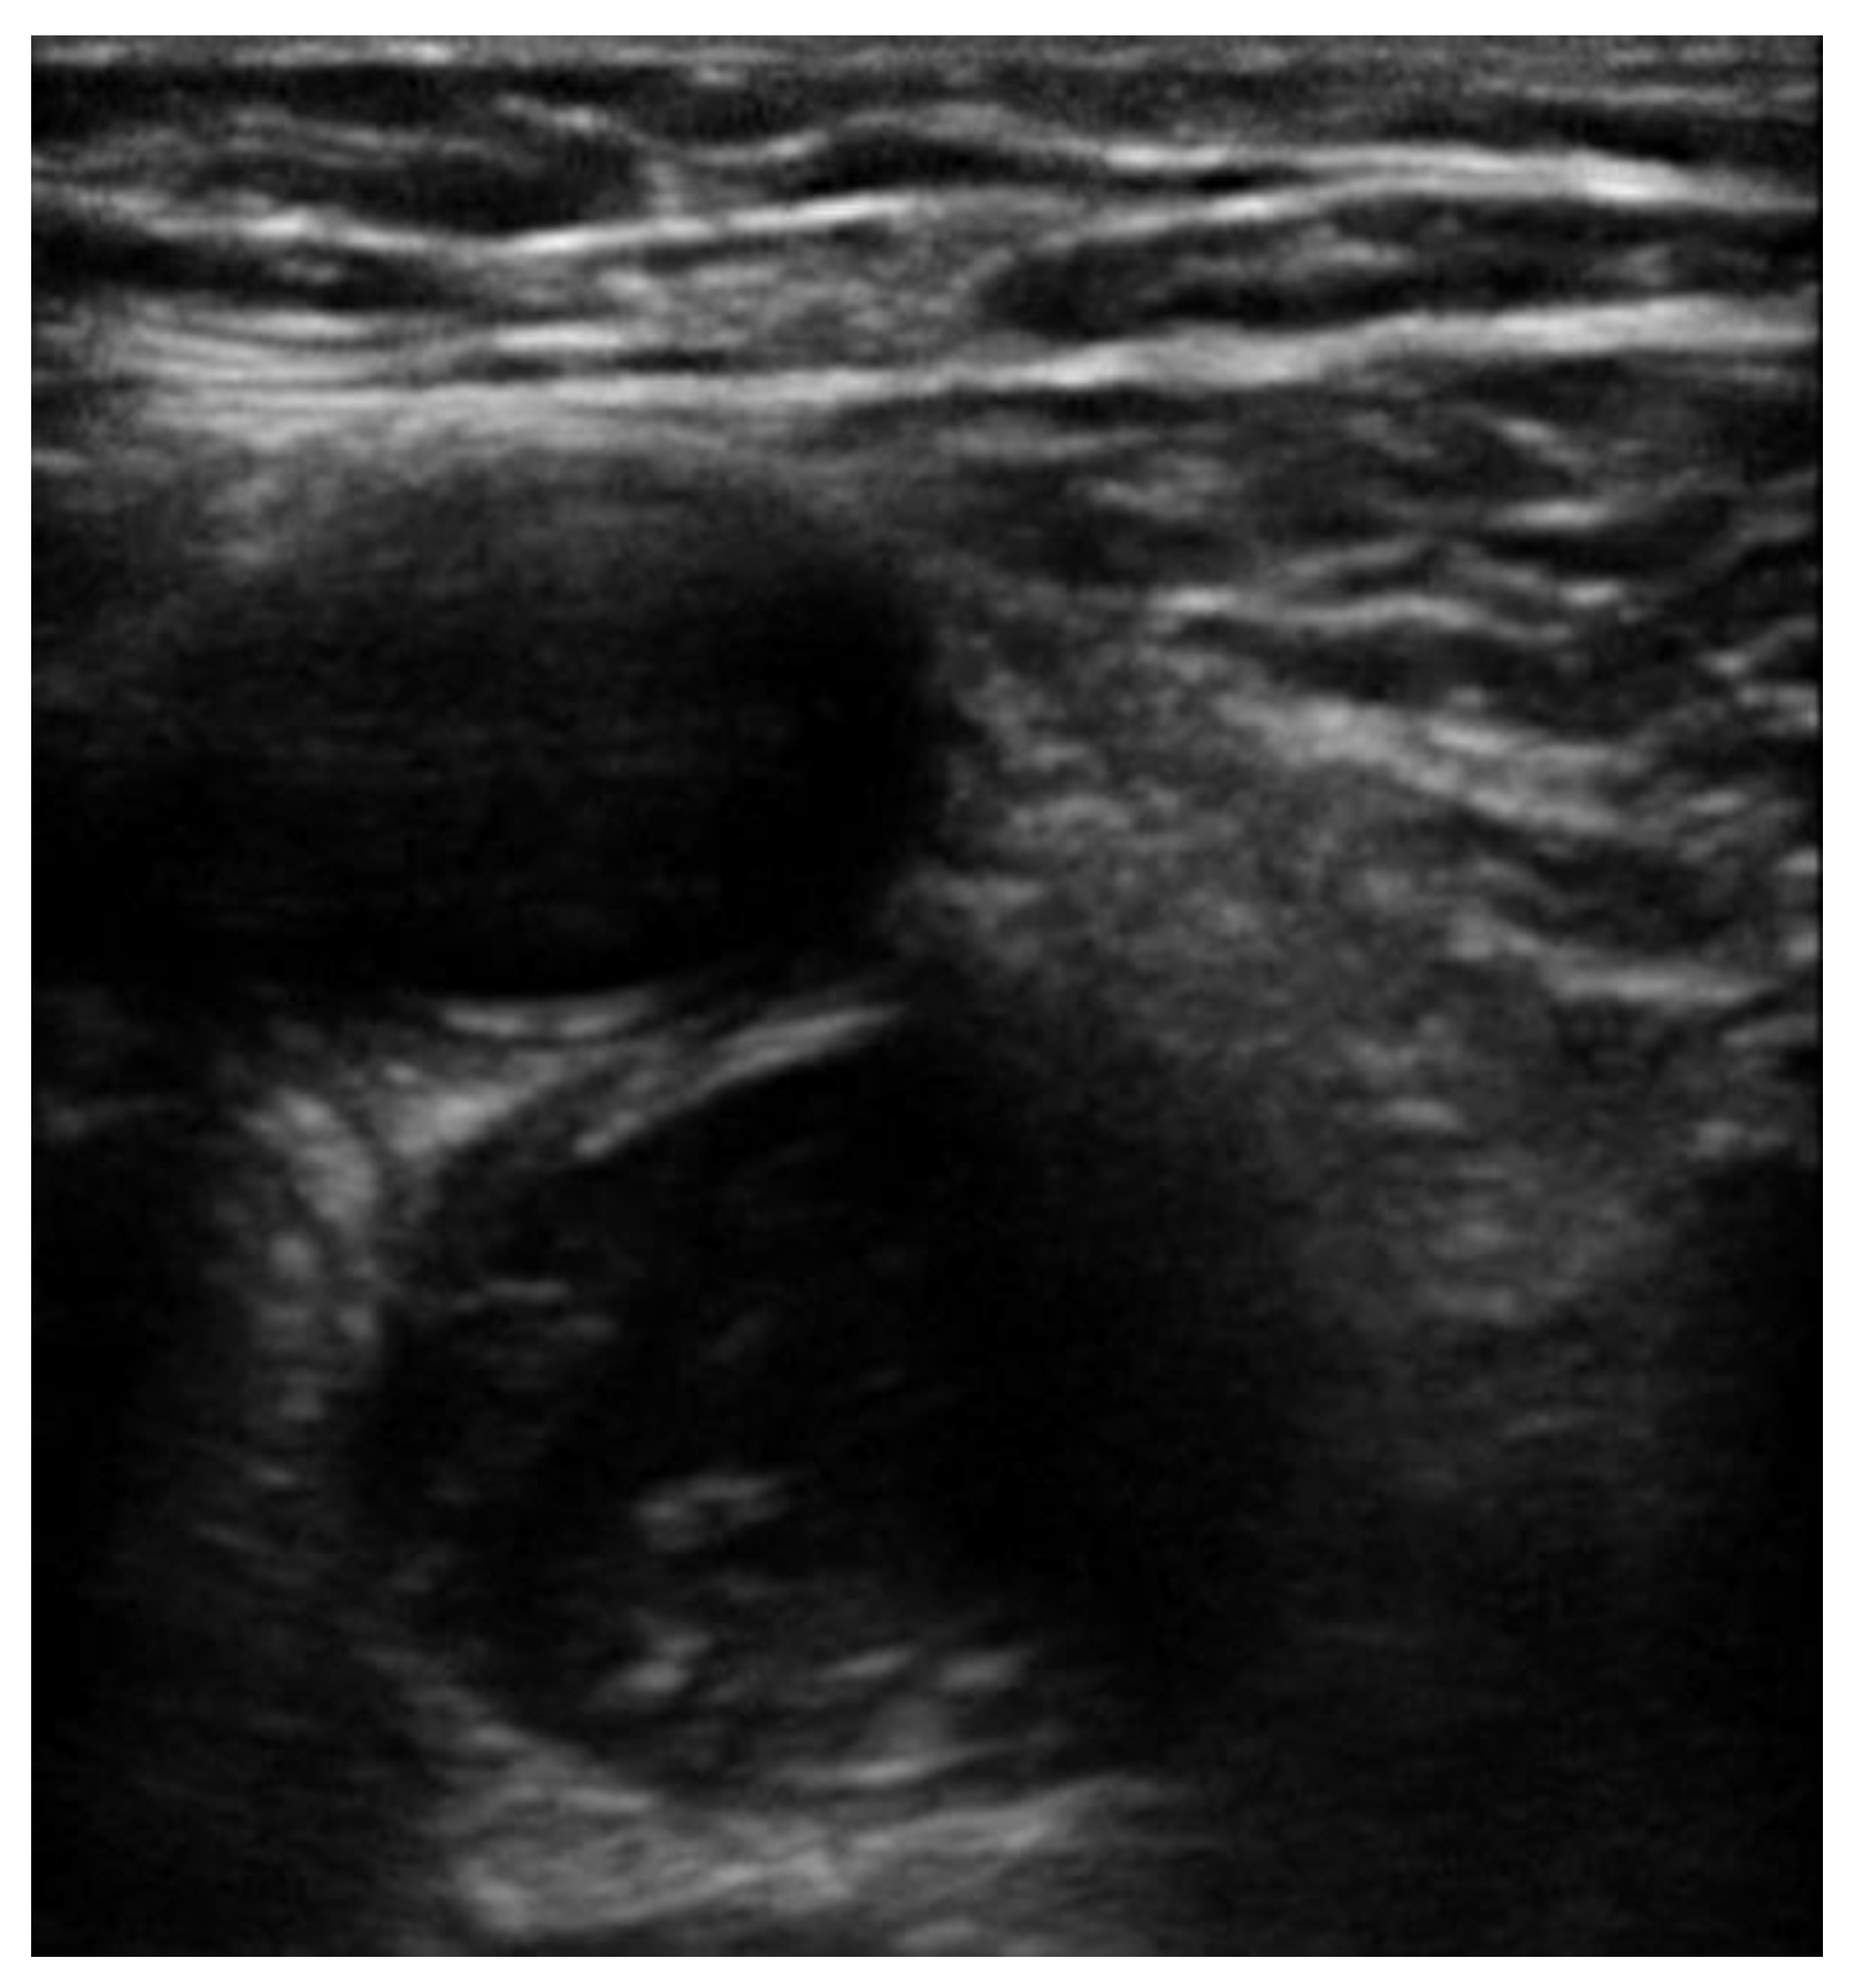

5. Protocols